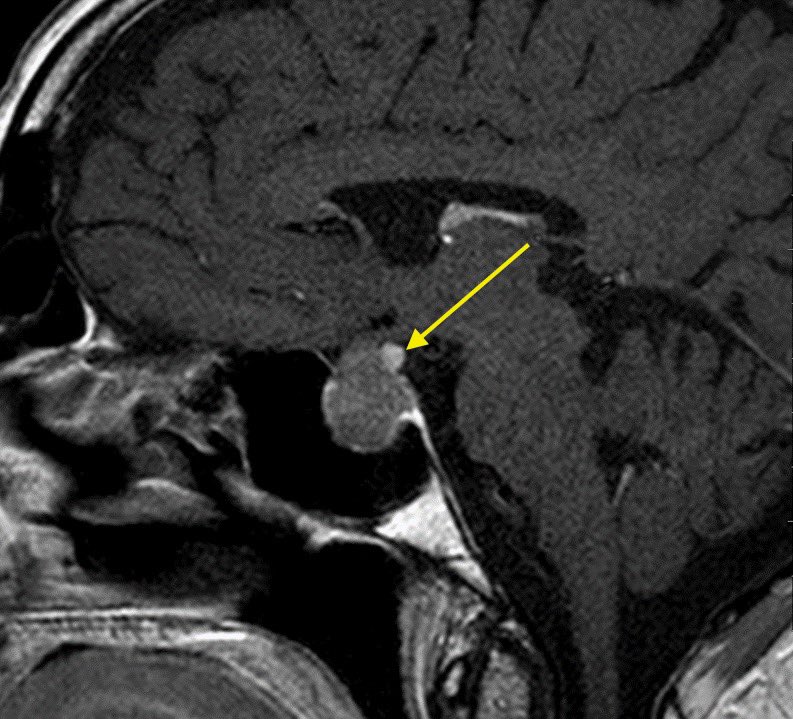

Is it sellar based? suprasellar (S)? clival? Planum sphenoidale (PS)? Tuberculum sellae (arrow)?

▶️Location can change operative approach including but not limited to subfrontal vs transsphenoidal